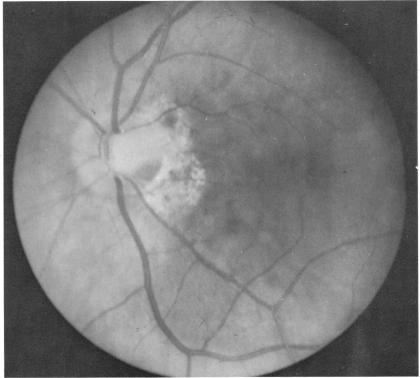

Six cases of congenital pit of the optic nervehead associated with posterior serous retinal detachment are presented. All were treated by photocoagulation along the disc margin in the area of retinal detachment. In five cases reattachment of the retina occurred, after the clinical development of a film chorioretinal adhesion at the disc margin, and appeared to be secondary to the treatment. The sixth case (Case 4), although treated, appeared to represent a spontaneous reattachment. This disorder, which frequently results in permanent decrease of central vision, affected the better, or only, eye in two of the six cases herein reported. Fluid, probably from the vitreous cavity, appears to gain access to the subretinal space via the pit. Reattachment in treated cases occurred only if an effective chorioretinal adhesion was created over the entire area of the fistulous detachment at the disc margin. Field defects after treatment appear to be secondary to either the optic pit itself or the longstanding retinal detachment, oftern accompanied by pigmentary degeneration and cystic macular degeneration, rather than juxtapapillary photocoagulation treatment.

本文报告6例先天性视神经乳头凹合并浆液性视网膜脱离。所有病例均采用视网膜脱离区域沿视盘边缘光凝治疗。5例视网膜脱离在视盘边缘形成脉络膜视网膜粘连后复位,似乎是治疗的继发结果。第6例(病例4)虽经治疗,但似乎是自发复位。这种疾病常导致中心视力永久性下降,在本文报告的6例中有2例影响了较好或仅有的一只眼。液体可能来自玻璃体腔,似乎通过视神经乳头凹进入视网膜下间隙。治疗病例中,只有在视盘边缘瘘管性脱离的整个区域形成有效的脉络膜视网膜粘连时,视网膜才会复位。治疗后的视野缺损似乎继发于视神经乳头凹本身或长期视网膜脱离,常伴有色素性变性和黄斑囊样变性,而非视盘旁光凝治疗。